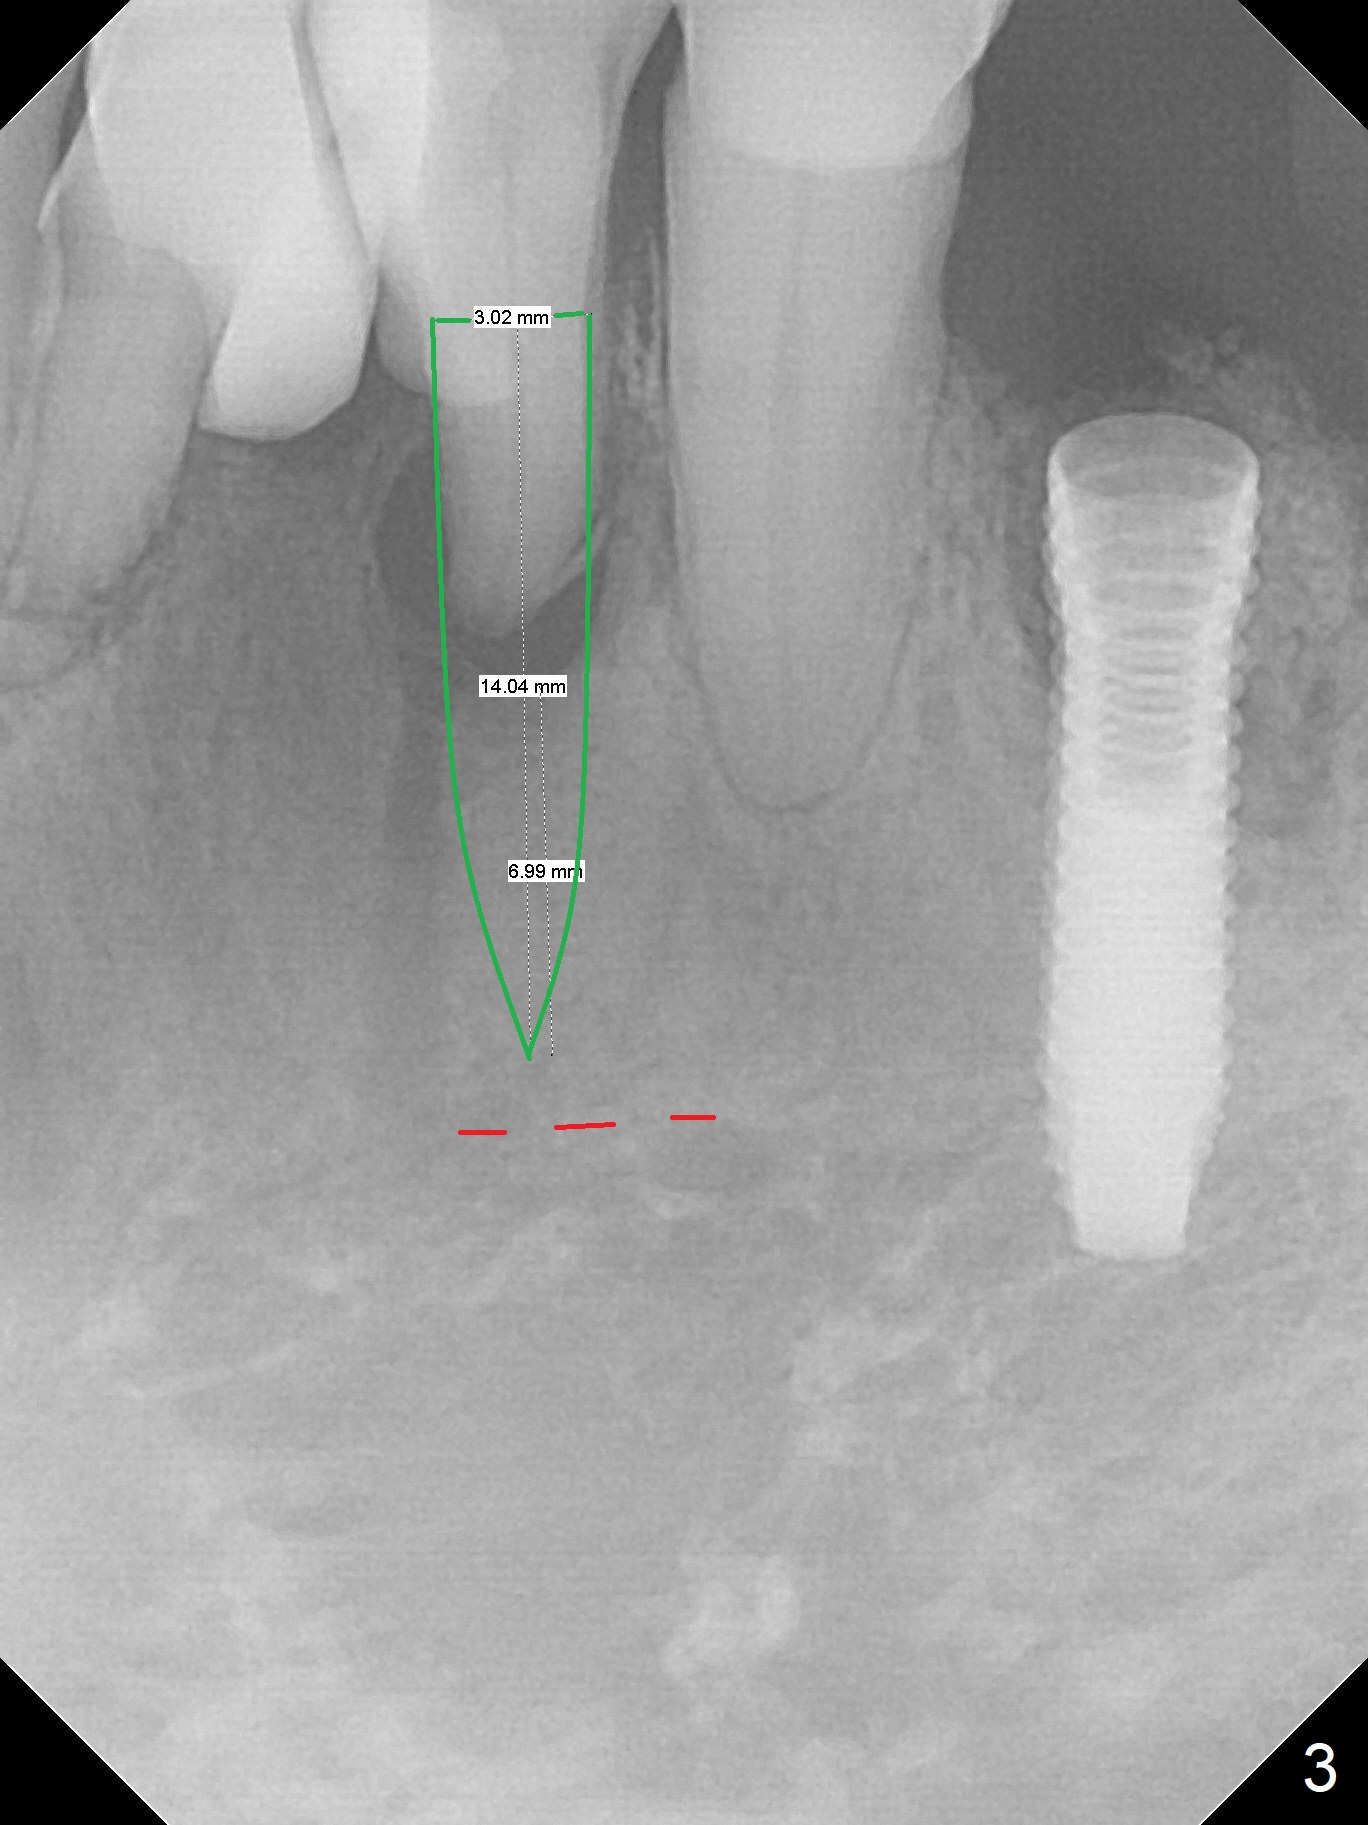

A 73-year-old man will return for #23 and 25 implants following ones at #21 and 31. Probably due to large periapical radiolucency at #23 (Fig.1 yellow dashed line), the terminal branch (pink) of the Incisive Canal (red) is distinct. Postop hemorrhage occurs associated with placement of a long implant at #. To prevent the complication at #23, a 14 mm long 1-piece implant (Fig.3) seems to be safer than 16 mm one (Fig.2). Seven mm in the native bone (Fig.3) should provide with sufficient primary stability. A temporary crown will be fabricated at #31. If the provisional at #21 is unstable, impression may be necessary for #21 and 31. Initiate osteotomy using visual and tactile acuity and double check the position and trajectory with RPD and X-ray. It might be preferable to extract the malpositioned incisor to give the remaining one the best 3-dimensional reference. Prepare 2 of 1-piece implant kits as well as angled one.